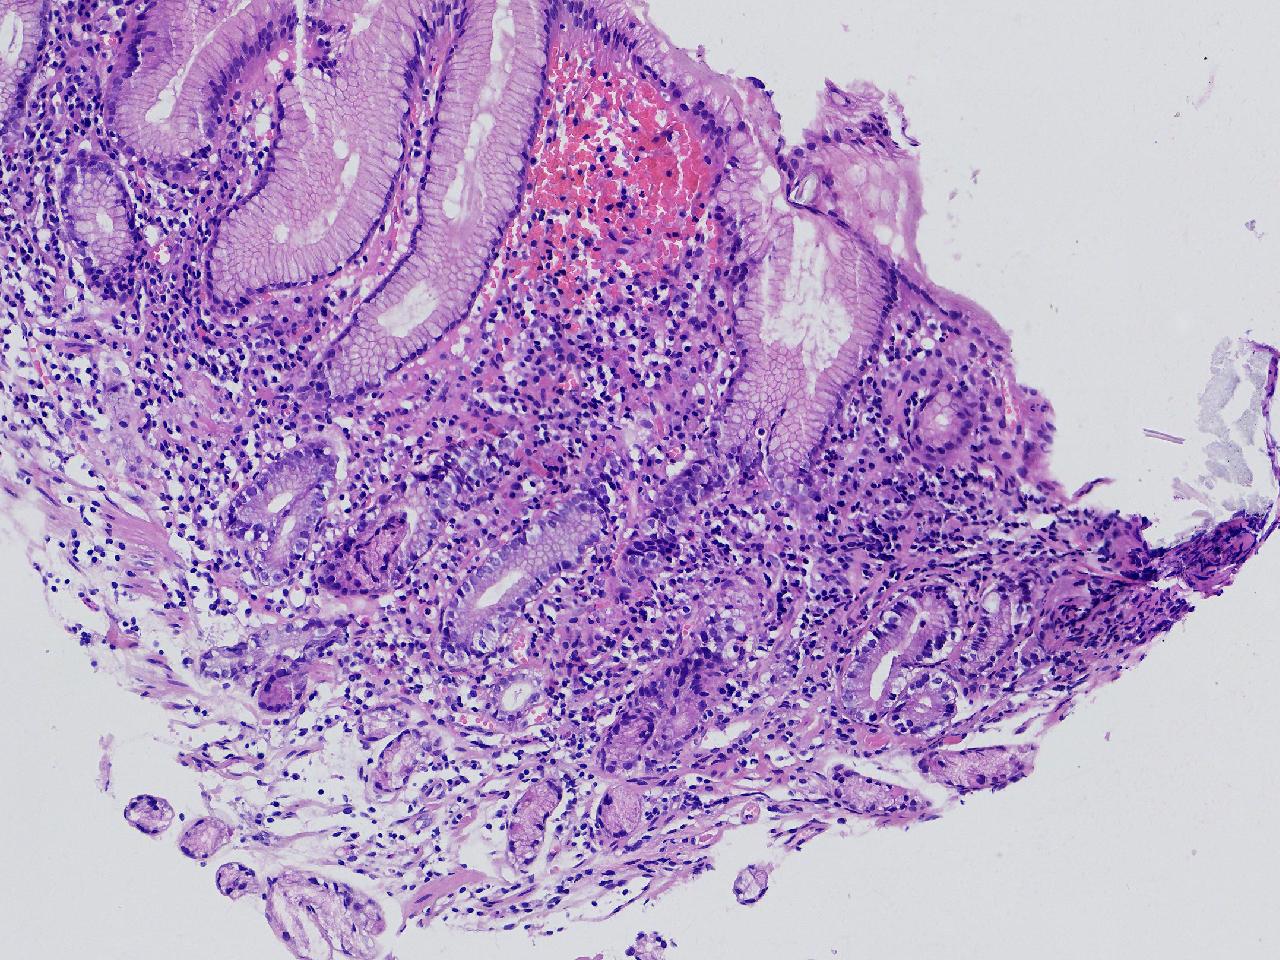

间质内是炎细胞吗?

男,49岁,胃镜活检,胃窦粘膜红白相间,以红为主,后壁见一直径约0.4cm大小片平隆起,表面糜烂,活检1块送检,质软弹性可。

胃窦活检

灰白色不整形软组织1块,直径0.2厘米。

幽门型粘膜中度慢性炎

是的,主要是淋巴细胞和浆细胞。